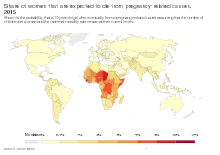

Complications

Per figures retrieved in 2015, since 1990 there has been a 44 per cent decline in the maternal death rate. However, according to 2015 figures 830 women die every day from causes related to pregnancy or childbirth and for every woman who dies, 20 or 30 encounter injuries, infections or disabilities. Most of these deaths and injuries are preventable.[112][113]

Maternal mortality and adverse health consequences

In 2008, noting that each year more than 100,000 women die of complications of pregnancy and childbirth and at least seven million experience serious health problems while 50 million more have adverse health consequences after childbirth, the World Health Organization (WHO) has urged midwife training to strengthen maternal and newborn health services. To support the upgrading of midwifery skills the WHO established a midwife training program, Action for Safe Motherhood.[5]

The rising maternal death rate in the US is of concern. In 1990 the US ranked 12th of the 14 developed countries that were analysed. However, since that time the rates of every country have steadily continued to improve while the US rate has spiked dramatically. While every other developed nation of the 14 analysed in 1990 shows a 2017 death rate of less than 10 deaths per every 100,000 live births, the US rate has risen to 26.4. By comparison, the United Kingdom ranks second highest at 9.2 and Finland is the safest at 3.8.[114] Furthermore, for every one of the 700 to 900 US woman who die each year during pregnancy or childbirth, 70 experience significant complications such as haemorrhage and organ failure, totalling more than one per cent of all births.[115]

In 2022, the WHO reported that the US had the highest maternal death rate of any developed nation while other nations continued to experience declines. The death rate of Black women has also continued to climb with a 2020 CDC report showing the maternal death rate at 55.3 deaths per 100,000 live births – 2.9 times the rate for White women.[116] In 2023, a study reported that deaths among Native American women were even higher, at 3.5 times the rate for White women. The report attributed the high rate in part to the fact that Native American women are cared for under a poorly funded Federal Health Care System that is so stretched that the average monthly visit lasts only from three to seven minutes. Such a short visit allows neither time for performing an adequate health assessment nor time for the patient to discuss any problems she may be experiencing.[117]

Epidemiology

The United Nations Population Fund estimated that 303,000 women died of pregnancy or childbirth related causes in 2015.[166] These causes range from severe bleeding to obstructed labour,[167] for which there are highly effective interventions. As women have gained access to family planning and skilled birth attendants with backup emergency obstetric care, the global maternal mortality ratio has fallen from 385 maternal deaths per 100,000 live births in 1990 to 216 deaths per 100,000 live births in 2015, and it was reported in 2017 that many countries had halved their maternal death rates in the last 10 years.[166]